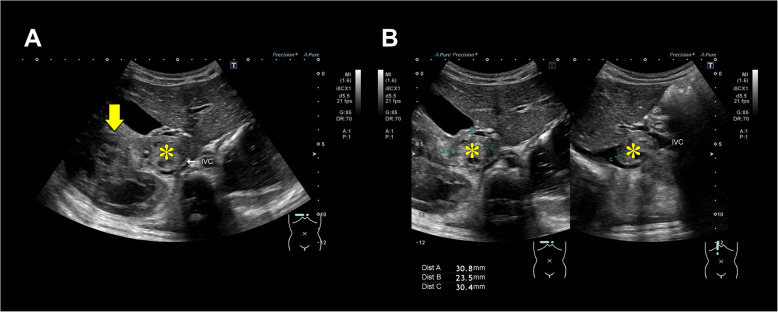

Case presentation: A 2-year-old boy with an IVC-extending Wilms tumor underwent nephrectomy. Anticipating hemorrhage, we employed an SL One® rapid infusion device via a Broviac™ central venous catheter. During a sudden, high-volume bleeding, transfusion was initiated at 23 mL/min and intermittently increased to 150 mL/min while preload was evaluated using transesophageal echocardiography, rapidly stabilizing hemodynamics. No rapid-transfusion-related complications, such as hyperkalemia or hypothermia, were observed, and the postoperative course was uneventful.